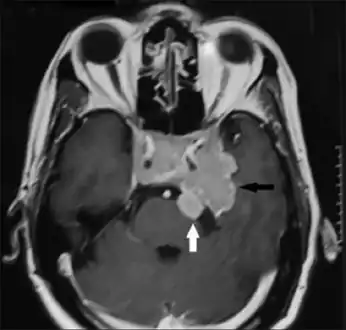

Invasive prolactinoma showing invasion into the left temporal lobe

Prolactinoma on MRI